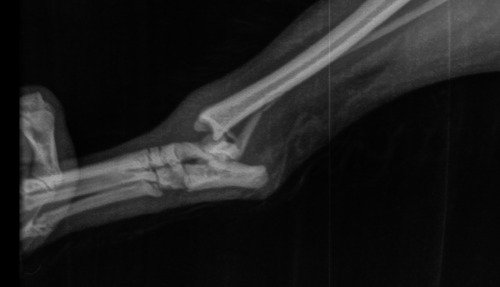

Ola eu sou o Simon de 7 aninhos e minha raça Sptiz Alemão. Sou muitooo traquina e peguei uma briga com meu irmãozinho porque estava com ciumes da minha mamãe humana. Torci, fraturei e rompi os ligamentos da minha patinha traseira a 10 dias atrás. Fui ao veterinário e o raio X constatou que meu caso é cirúrgico 😥. Estou com minha patinha imobilizada e sentindo fortes dores porque minha mamãe não esta em condições de arcar com a cirurgia que custa aproximadamente

R$ 4.000 isso inclui (exames, cirurgia, anestesia, pós cirúrgico e medicações)

Minha mamãe ja gastou bastante quando me machuquei e não tem mais recursos para realizar minha cirurgia e dar continuidade no meu tratamento

Conto com a ajuda de todos porque essa tal de fratura dói 😢